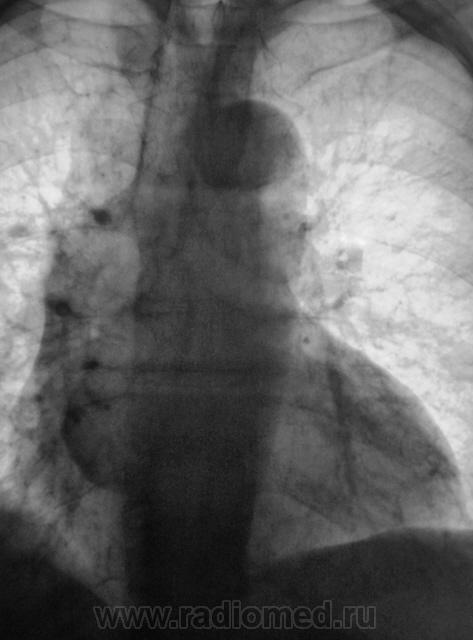

1 срез.

похоже в просет "что-то" растет, наверное показана бронхоскопия? А дополнительная тень не ушко правого предсердия?

Хорошие томограмы, жаль нет бочка посмотреть вентиляцию нижней доли, а так конечно в просвете бронха дополнительная тень, предсердие бы оттеснило весь бронх. Надо рекомендовать бронхоскопию.